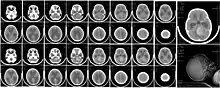

Diagnostic

Le diagnostic se fait via un examen neurologique et souvent via le scanner qui permet de différencier une lésion (accident vasculaire) d'une tumeur et d'en préciser le stade, la localisation, le caractère éventuellement multiple. En cas de doute, une biopsie cérébrale est faite, sous anesthésie générale, grâce à une aiguille à ponction guidée grâce à un repérage 3D préparé grâce au scanner. Des métastases invitent à rechercher et traiter le cancer d'origine (dosages sanguins, marqueurs biologiques et éventuelle coloscopie, scanner, fibroscopie pulmonaire, une mammographie sont alors prescrites par le cancérologue).